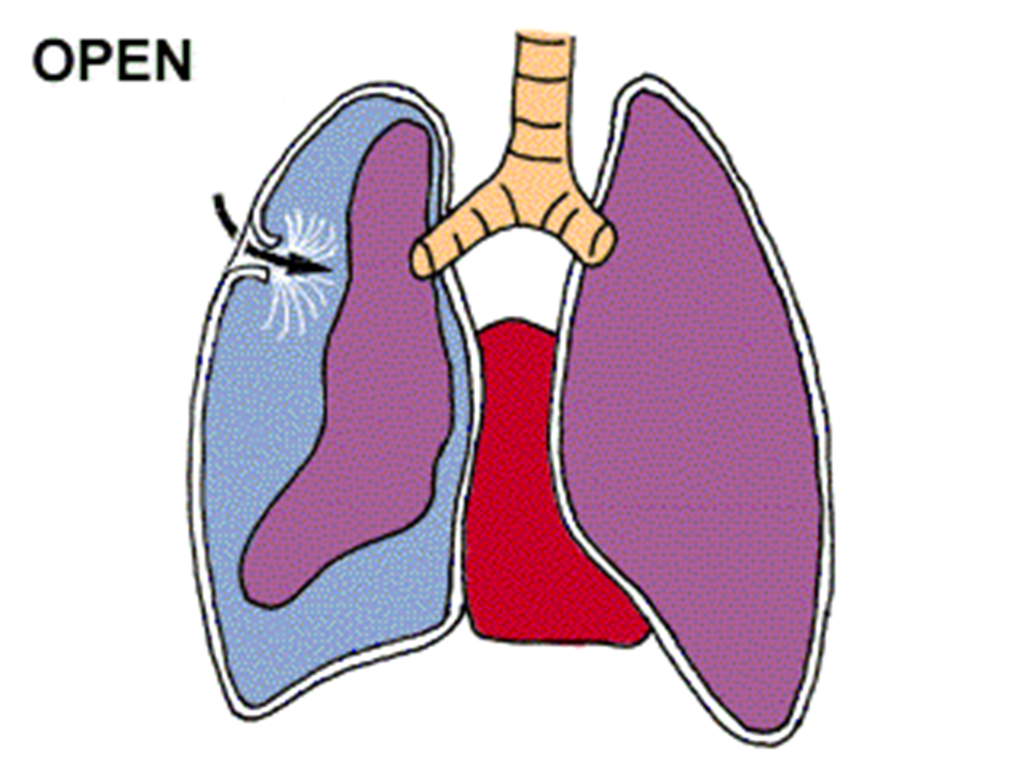

Схемы дыхания: Пневмоторакс на изображениях